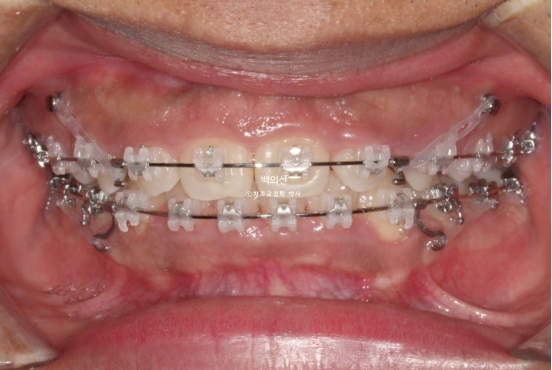

23.11

치료시작 4개월차 입니다.

앞니를 위로 올려 뼛속 방향의 이동인 함입을 도모하게 되면 잇몸도 치아와 함께 올라가며 웃을 때 잇몸노출량이 줄어듭니다.

이를 위해 교정용 나사가 필요합니다.

24.06

치료시작 1년 차 과개교합은 해소가 되었습니다.